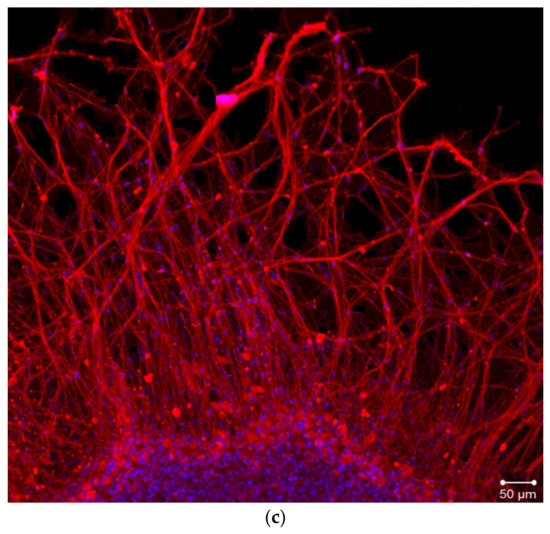

2.2. Organotypic Tissue Culture

4.3. Organotypic Nerve Tissue Culture Method

4.4. Immunostaining